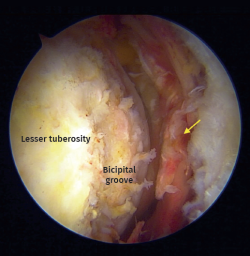

Figure 2. Arthroscopic view from anterolateral portal on a right shoulder in beach chair positioning. Chronic biceps tendon rupture. Arrow: Full-thickness and retraction of the subscapularis tendon

Figure 5. Arthroscopic view. Full-thickness subscapularis tear with medial instability of the long head of the biceps tendon. Asterisk: biceps tendon. Arrow: torn subscapularis tendon.